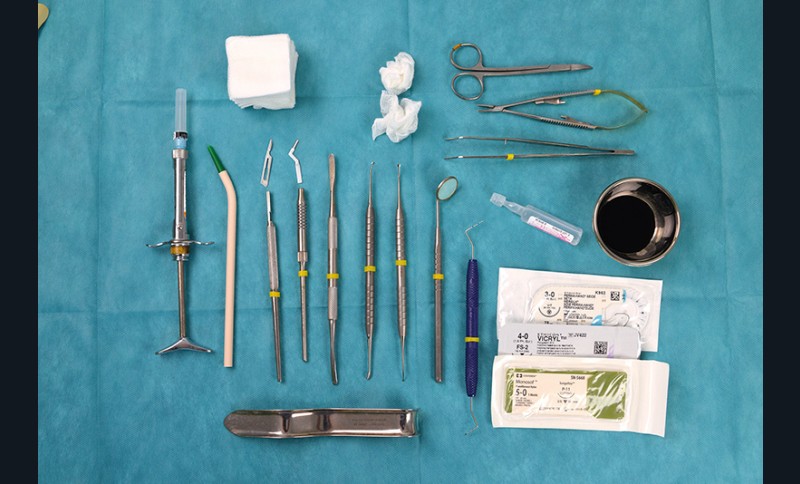

Le matériel

Matériel de chirurgie plastique parodontale dont : lame 15C et lame MJK 3 plate, décolleur rond pour tunnélisation Zepf® (Kerr), sutures 5.0 Monosof® (Covidien), 4.0 Vicryl® (Ethicon) et 3.0 soie® (Ethicon), sérum physiologique et bétadine.